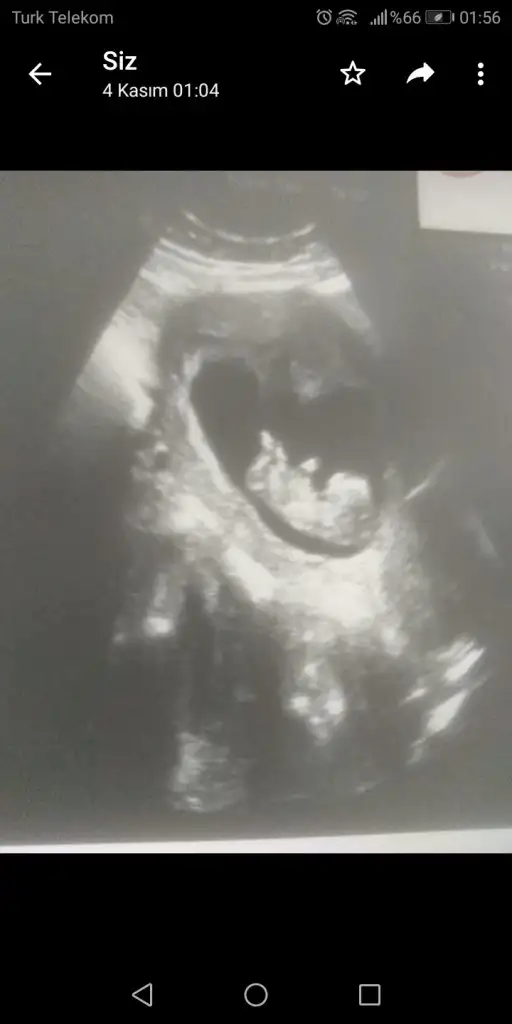

Erkek diyorumEki Görüntüle 2553261

merhaba, ben de tahmin rica edebilir miyim? 11 hafta 2 günlük bebeğim :)

Teşekkür ederim yorumunuz için :) ikra meyra’dan da tahmin alabilir miyim?Erkek diyorum

KızEki Görüntüle 2553261